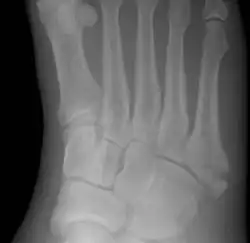

![]() | |

| Jones fracture as seen on Xray | |

The fracture typically occurs when the toes are pointed and the foot bends inwards.[6][2] This movement may occur when changing direction while the heel is off the ground such in dancing, tennis, or basketball.[9][10] Diagnosis is generally suspected based on symptoms and confirmed with X-rays.[3]

Diagnostic X-rays include anteroposterior, oblique, and lateral views and should be made with the foot in full flexion.